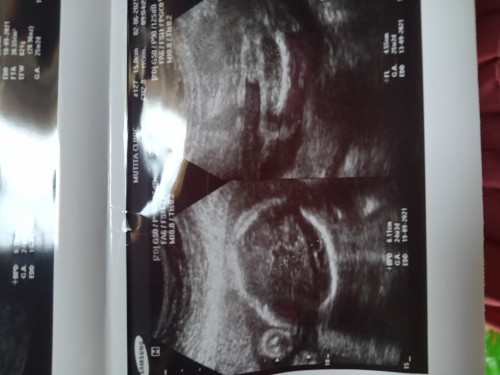

ดูไม่ออกเลยค่ะ คุณหมอได้แจ้งไหมคะว่าเพศอะไร ถ้าไม่แปลว่ายังไม่รู้เพศ ถ้าแจ้งแล้วเพศก็ตามที่หมอบอกเลยค่ะ เพราะใบซาวด์แม่ๆทั่วไปอ่านไม่ออกแน่ๆค่ะแบบนี้😊

24สัปดาน้ำหนักน้อง821กรัมเยอะมั่ยค่ะ